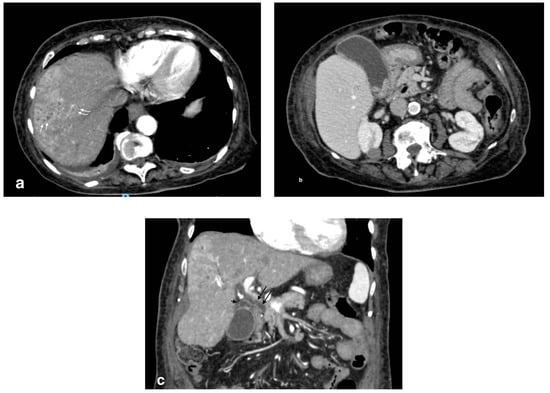

In the context of acute cholecystitis, the formation of liver abscess is an event strictly related to a gallbladder perforation. It can be differentiated in pericholecystic and parenchymal abscesses. The leakage of bile and other material from the gallbladder lumen can undergo infection (it could also be already infected) and finally organize in a mass, sometimes multiloculated, with a rounded contour and a more or less thick capsule, which can be collected in the pericholecystic space or, distally, in the liver parenchyma. Pericholecystic abscess as a complication of acute cholecystitis is reported in 3%–19% of cases [17]. The typical presentation consists in the evidence of intramural and pericholecystic rim-enhancing fluid collections, with the omentum often adherent/thickened (Figure 8). The abscess can be unilocular or have septations and an irregular contour [17]. Liver abscesses are classified by size: macroabscesses are more than 2 cm in diameter, and microabscesses are less than 2 cm in diameter [15]. Pathogenically, liver abscesses could also originate from an ascending infection from the biliary system [20]; in this case, MDCT reveals the presence of gallstones obstructing the biliary duct and/or suppurative cholangitis. After contrast injection, peripheral contrast enhancement is often shown (the so-called “rim sign”) (Figure 9). The presence of intralesional air is almost pathognomonic, despite being not always detectable.

Figure 9.

Liver abscess with pylephlebitis: (a) CT arterial phase; (b) CT portal phase. In the right lobe, V segment, a large hypodense collection with hypoattenuating halo due to intrahepatic abscess (black arrows, (a,b)) with the presence of a hypodensity within the left portal vein lumen due to thrombosis and hyperdensity of portal walls indicative of pylephlebitis better defined in CT portal phase (b) (white arrow).